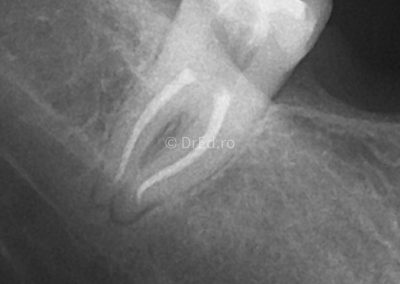

Galerie

Toate imaginile, fotografiile și radiografiile publicate pe acest site sunt protejate prin drepturi de autor și constituie proprietatea exclusivă a Dred.ro.

Aceste materiale sunt furnizate exclusiv în scop informativ și educațional și nu conțin date cu caracter personal sau informații care permit identificarea pacienților, în concordanță cu legislația privind protecția datelor cu caracter personal și GDPR.

Reproducerea, copierea, distribuirea, publicarea, transmiterea, modificarea sau orice altă utilizare, integrală ori parțială, a acestor materiale, în orice formă și prin orice mijloace, fără consimțământul prealabil scris al titularului drepturilor, este strict interzisă și poate atrage răspunderea civilă și/sau penală, în condițiile legii aplicabile privind drepturile de autor și protecția proprietății intelectuale.